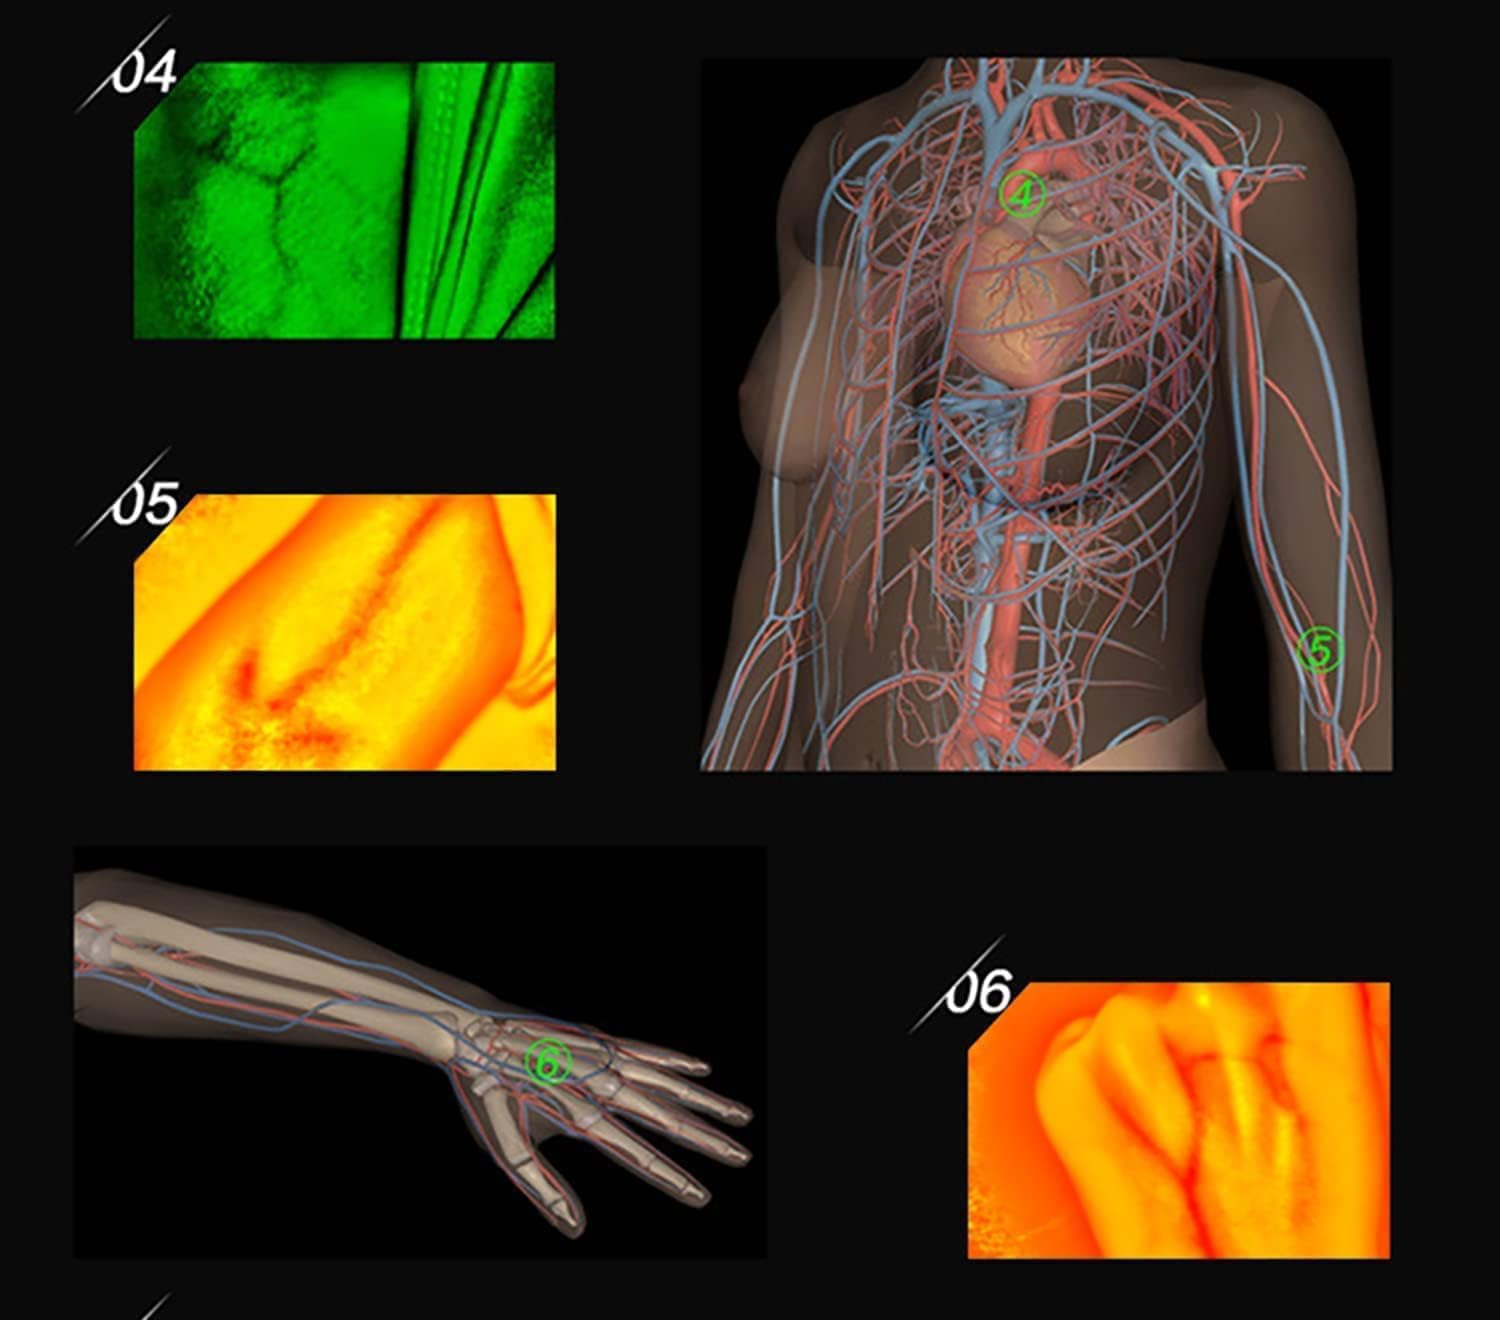

Our medical vein finder device adopts the principles of hemoglobin strong absorption of infrared light,

designed the helpful vein finder device, which consists of infrared vein collector & vein recognition system